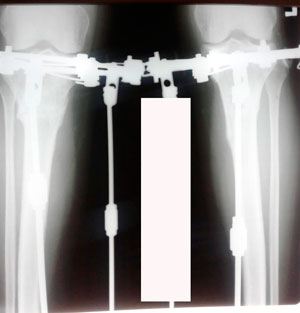

Дата операции - 20.03.2020

Дата снятия аппаратов - 26.06.2020

Вложения

image-26-06-20-12-42-1.jpg

image-26-06-20-12-42.jpg